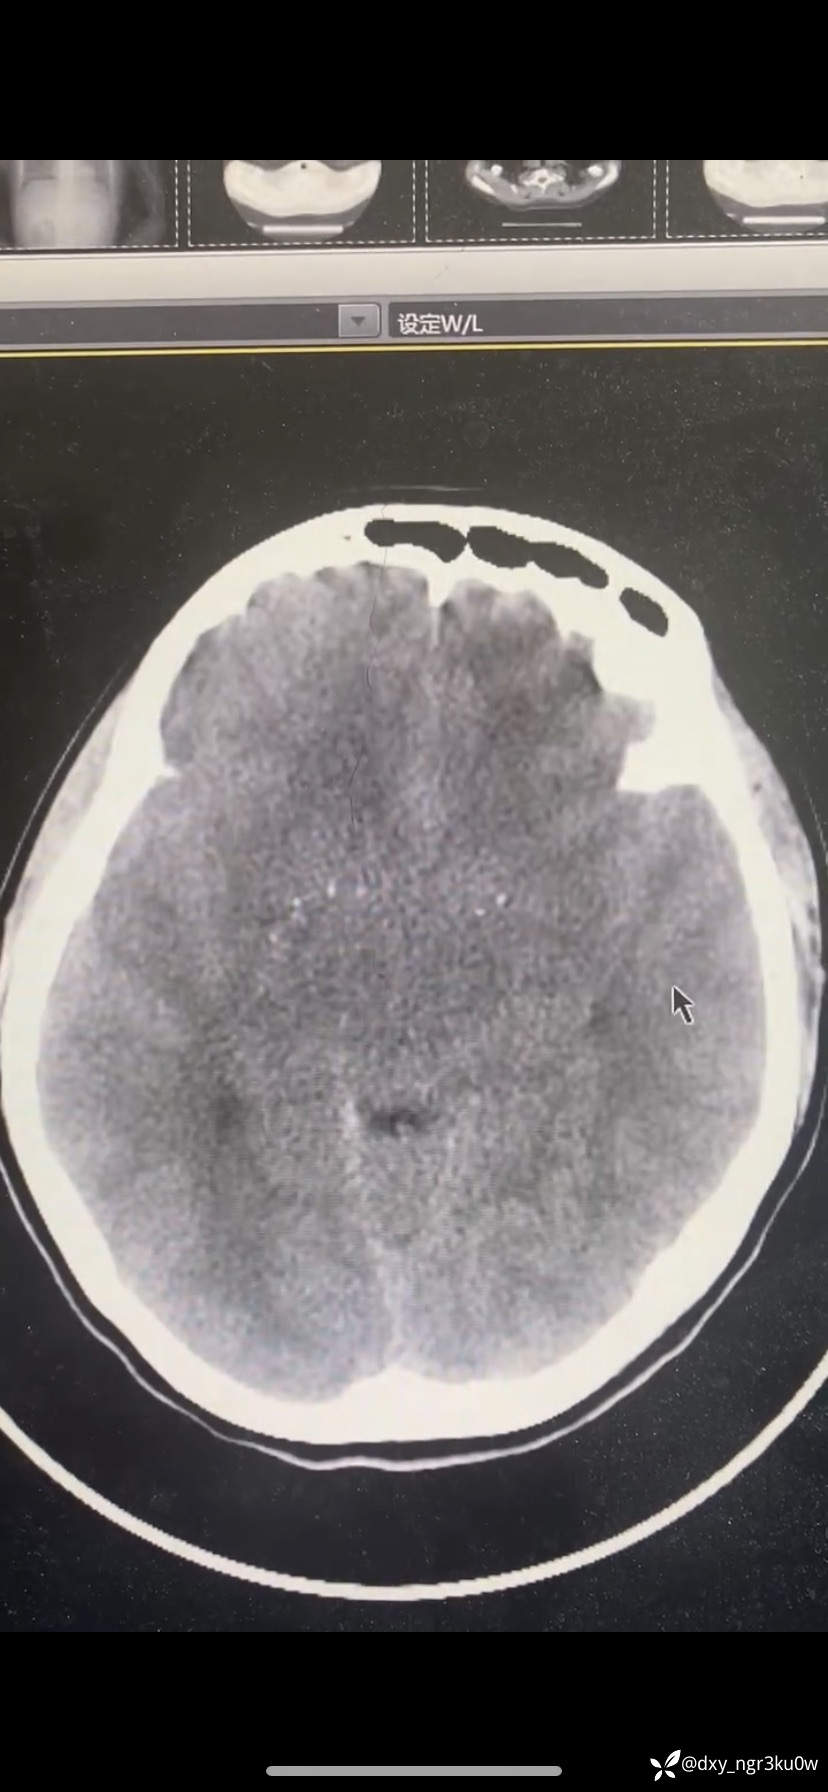

入院血气分析:ph:7.001,PCO2 10.7,PO2 136.6,Na124,K5.18,HCO3- 2.6,Glu>30,Lac1.7。颅脑CT如下